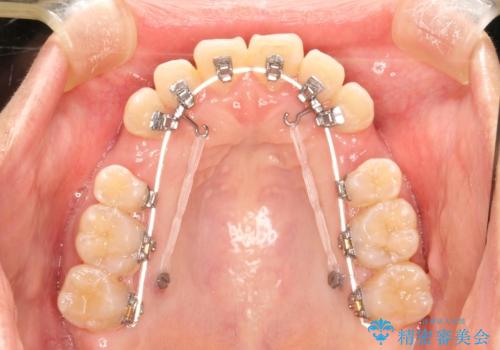

上下の歯のガタガタ ワイヤーでの抜歯矯正で整った歯並びへ

- 矯正装置

- 審美装置

- 上下の歯のガタガタを治したいとのことで来院されました。

がたつきの度合いが強いのと、口元をなるべく引っ込めたい希望がありましたので、ワイヤーでの抜歯矯正となりました。

ガタガタが重度の方は抜歯が必要となることが多いです。

抜歯スペースを使って前歯を引っ込めることにより、口元の突出感も改善できました。